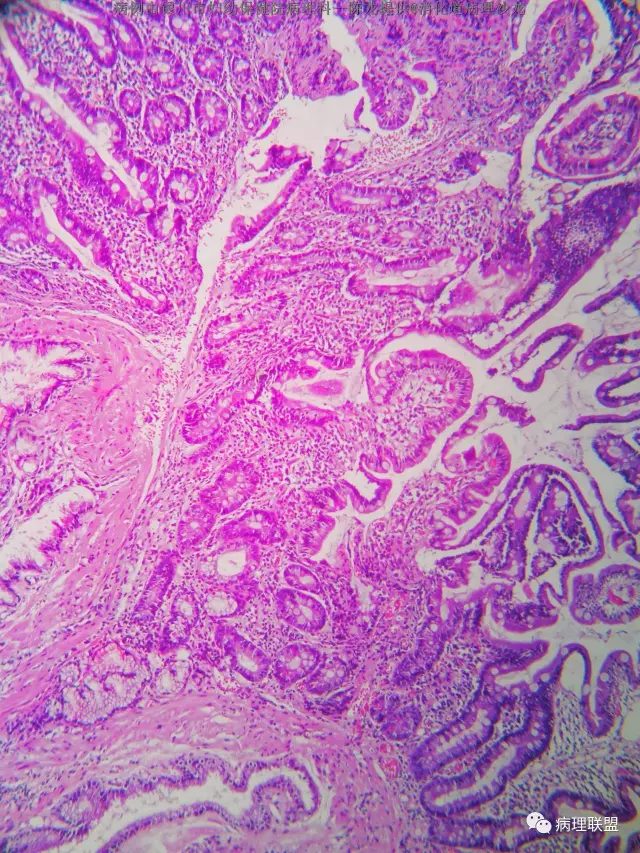

男性 68 十二指肠息肉 大小约3个0.4

(病例由银川市妇幼保健院病理科—陈龙提供,致谢!)